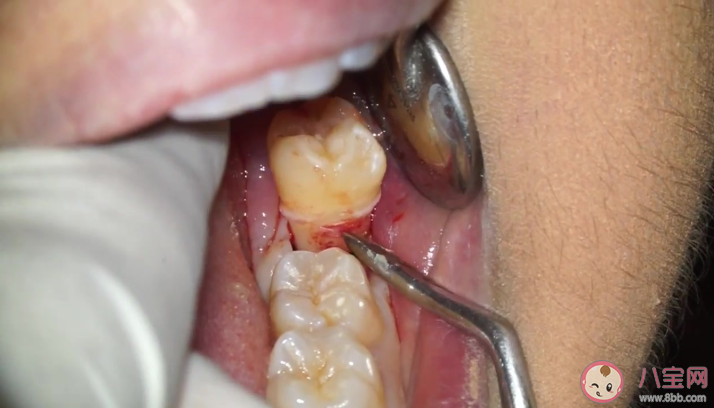

智齿是人口腔中的第三颗磨牙,智齿并不是没有用,如果其形态和位置正常,是可以行使正常的生理咀嚼功能的。但是有的智齿只能部分萌出或完全不能萌出,甚至以后也不能萌出的,就往往会危害口腔健康。由于智齿位置靠后不易清洁,容易滋生细菌,久而久之会腐蚀邻牙,造成智齿“不仅自己烂掉,还把前面邻牙一起带坏”的严重后果。

一般来说,13~30岁是拔智齿的最佳时期。在30岁前拔智齿比较合适,40岁后再拔创伤会增大。原则上一旦发现智齿发育不良,应尽早拔除。有的智齿已经连累周边牙齿坏掉,不得不两三颗牙一起拔掉,那时伤害就更大了。